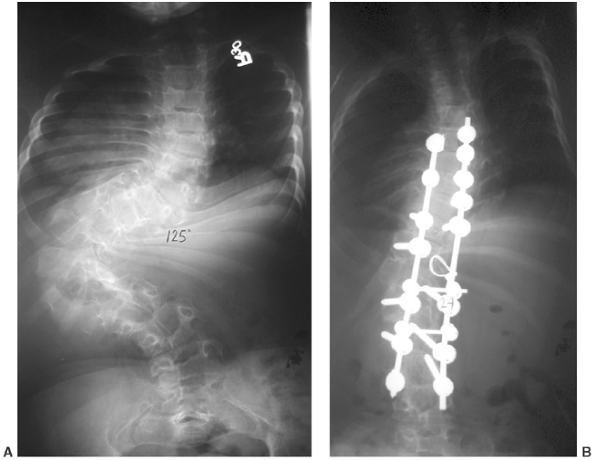

of the lumbar spine, unlike in achondroplasia. Scoliosis may occur in

the form of either a sharp, angular curve or a gradual, idiopathiclike

one (Fig. 8.18).

![]() |

Figure 8.18 Significant scoliosis may occur early in diastrophic dysplasia, as in this 125-degree curve in an 8-year-old child (A). After correction (B).

|